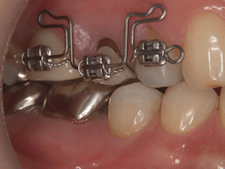

症例.8 インプラントと矯正治療

を用いた咬合再構成

| 術前 | 術後 |

|---|---|

|

|

| 治療前 | 治療後 |

|---|---|

|

|

| 年齢・性別 | 40代男性 |

|---|---|

| 主訴 | 歯が欠けてしまった |

| 治療期間 | 1.5年 |

| 治療内容 | 自費診療 補綴(詰め物、被せ物)9本:約100万円 インプラント2本:約100万円 矯正治療:約35万円 保険診療 咬合基本治療 |

| 費用 | 235万円 |